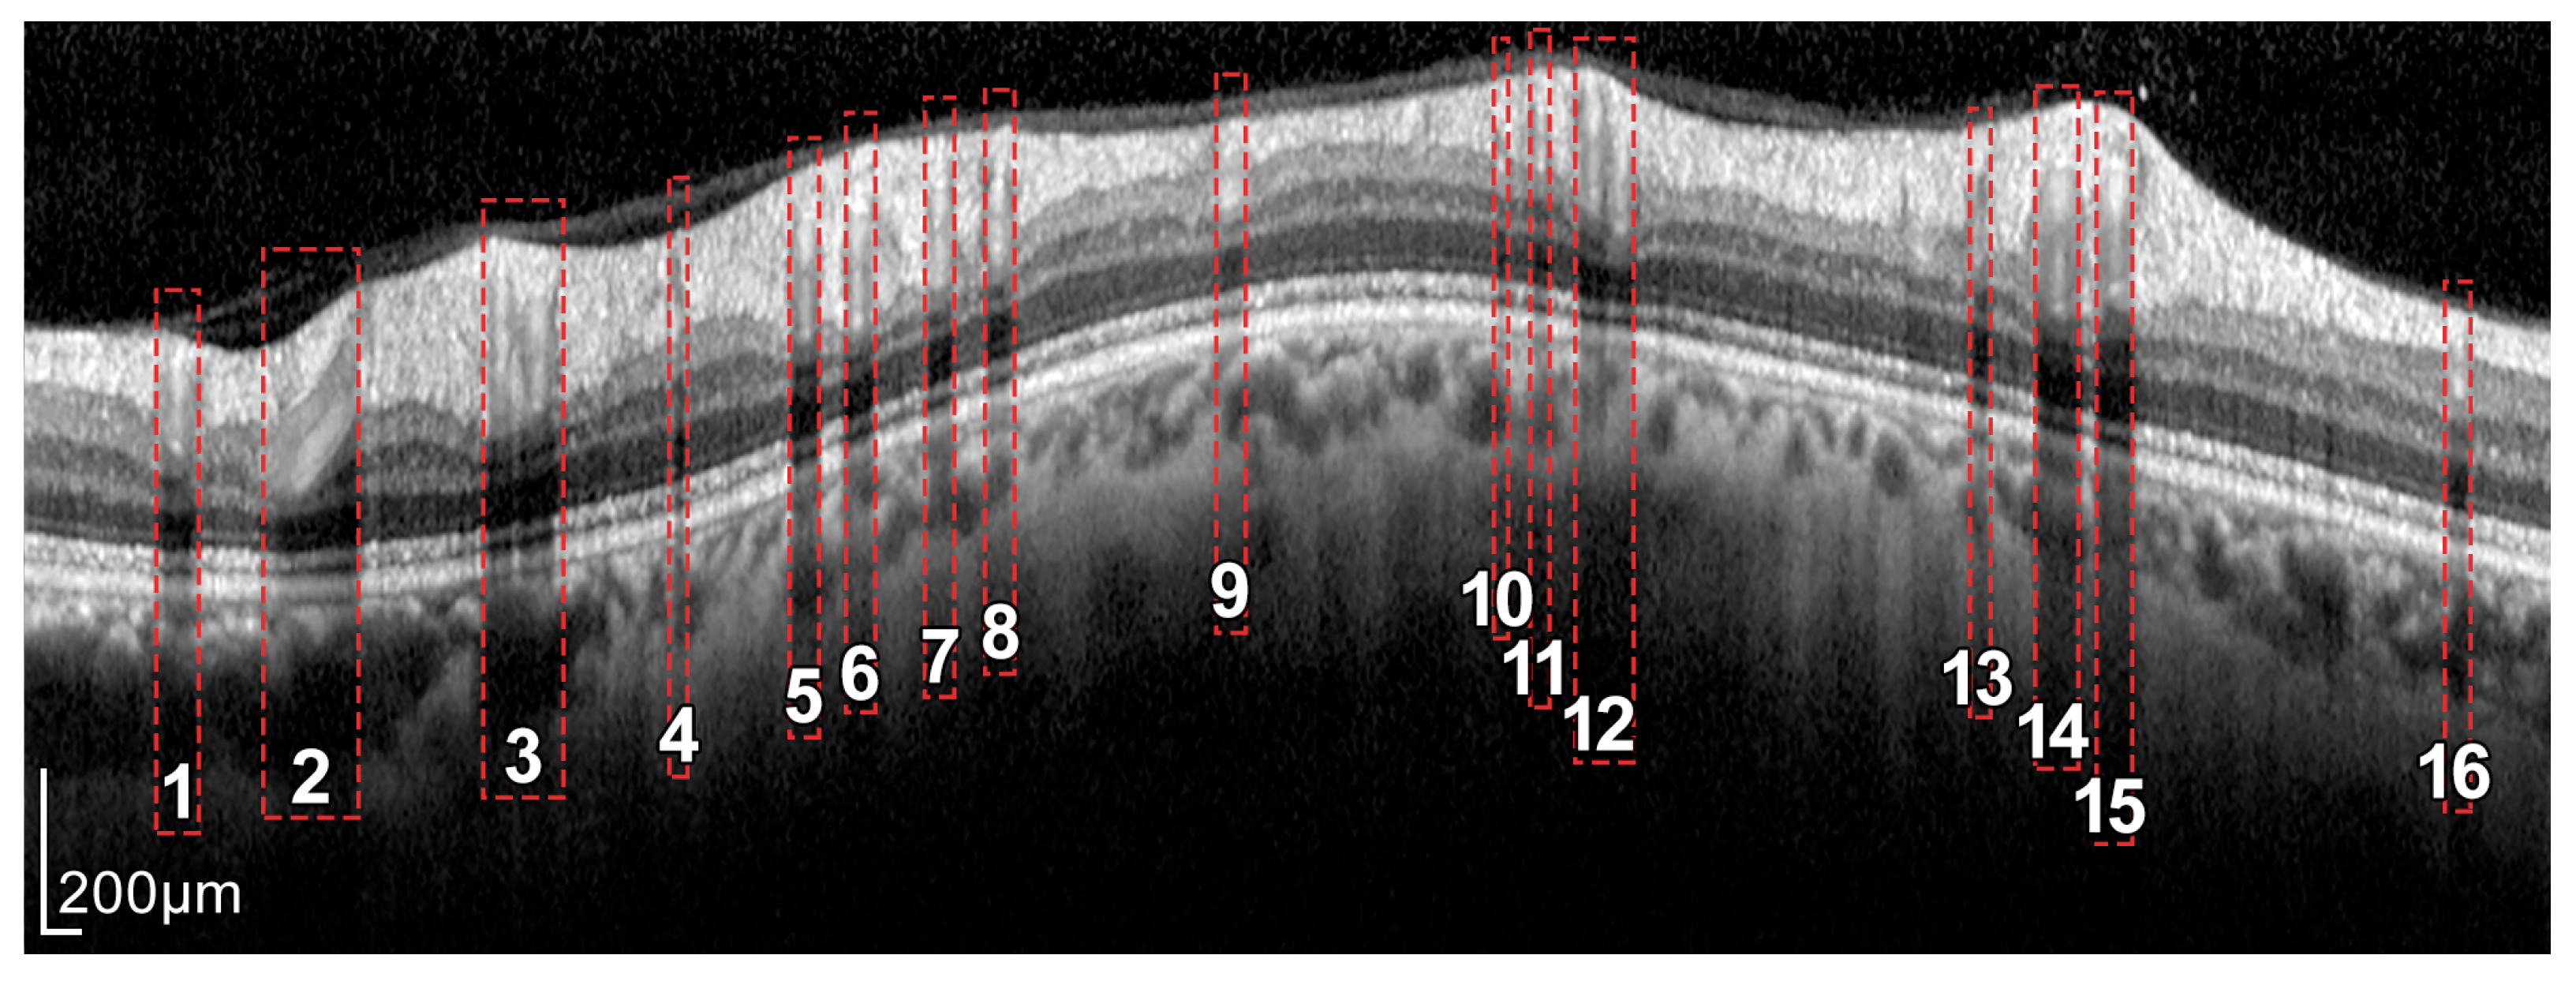

Figure 4.

Layers of the retina from top to bottom. RNFL: retinal nerve fiber layer; GCL: ganglion cell layer; IPL: inner plexiform layer; INL: inner nuclear layer; OPL: outer plexiform layer; and ONL: outer nuclear layer. Boundary delineation in the segmentation process. #1-UB: upper boundary of the RNFL; #2-AB: auxiliary boundary corresponding to the lower boundary of the ONL; #3-LB, lower boundary of the RNFL. The dashed boxes exemplify some of the artifacts of the layers.

In addition, because blood vessels are located just above the retina, a shadowing effect appears on the retinal layers. As observed in Figure 5, these vessels cross the circumference of analysis perpendicularly, casting a shadow on the retinal layers at these crossing points. This results in intensity inhomogeneities, boundary artifacts, and darkened areas in the layers to be segmented, as portrayed in Figure 6. This further complicates the segmentation of the RNFL and hence the calculation of its thickness.

Figure 6.

Intensity inhomogeneities and boundary artifacts caused by shadows cast by blood vessels. The numbers identify each of the vessels crossing the circular ray tracing depicted in Figure 5.